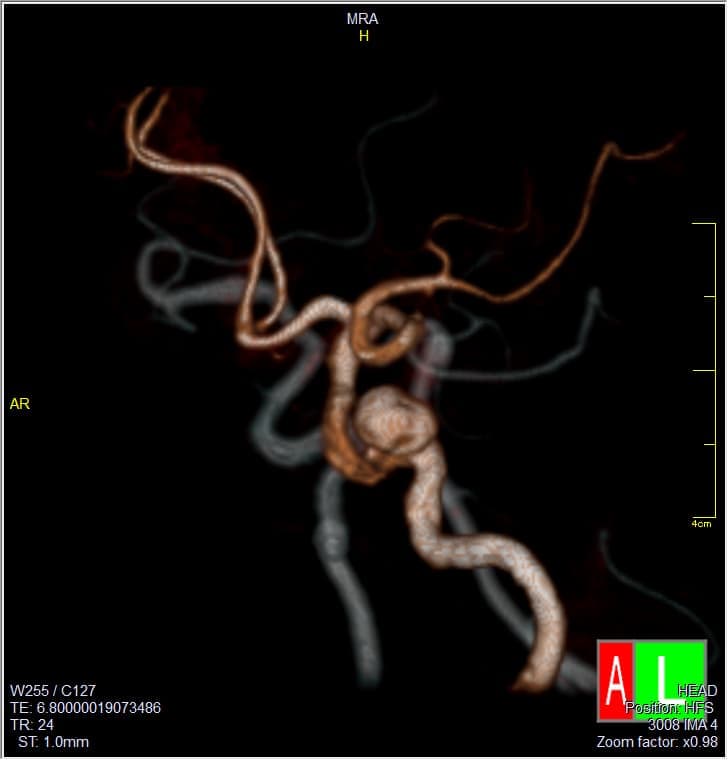

2. 脳ドック健診:脳血管の異常などを中心に検査します。